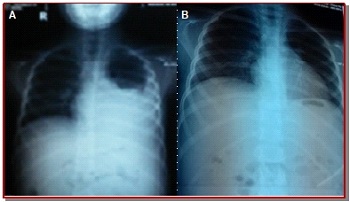

A 9-year-old girl presented with jaundice, abdominal distension, hematemesis, melena and pleural effusion

A 9-year-old girl of non-consanguineous parents presented at the outpatient department with the history of jaundice and abdominal distension for 20 days and respiratory distress for 7 days. She also complained of bloody vomiting without any melena. The mother gave the history of abdominal pain for 2 days which was diffuse in nature. Her menarche had not started yet. Her younger sister is healthy. She had no history of fever, constipation, family history of liver disease, sib death, contact with known tuberculosis patient, blood transfusion or parenteral medication. On examination, she was afebrile, moderately pale, dyspnea and leukonychia. Bilateral pedal edema was present.